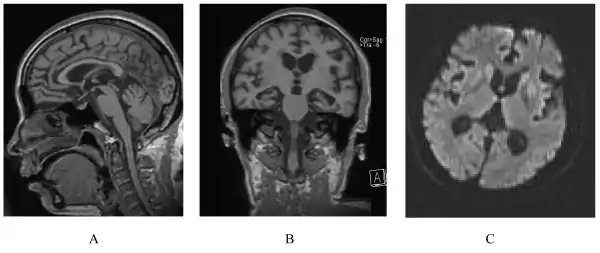

A person with inherited prion disease has cerebellar atrophy. This is highly typical of GSS.